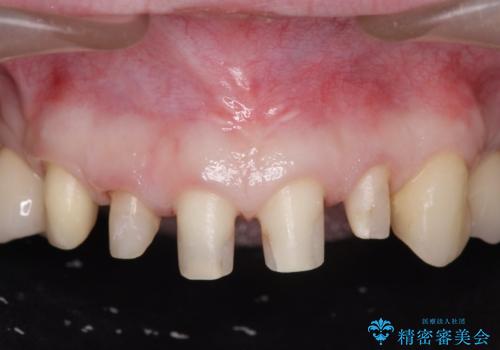

- 放置した虫歯の歯がボロボロになってしまい治療を希望され来院されました。

残根状態の歯、神経まで虫歯が達し失活した歯、歯肉縁下まで及んだ虫歯が多数認められます。

まず虫歯を拡大鏡、マイクロスコープ下で丁寧に取り除き歯肉縁下の虫歯を歯周外科により解決したのち、ジルコニアクラウン製作を行っていきます。